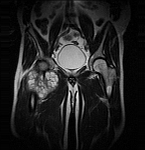

- Extensive reconstructive procedures for the reconstruction of large pelvic bone defects

The presentation of findings, X-ray images and CT or MRI can also be made by the attending physicians by mail or e-mail to the above-mentioned contact persons.